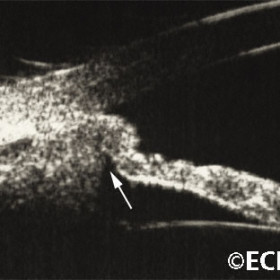

Choroidal melanoma

Choroidal Melanoma- 10 MHz B-scan ultrasound reveals choroidal excavation (arrow) at the base of this melanoma.